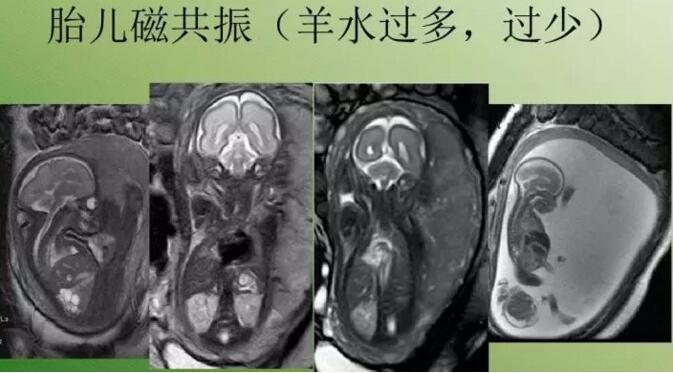

磁共振可解决羊水太少超声不好显示的问题

磁共振检查不受胎儿骨骼及羊水量的影响,对胎儿中枢神经系统、羊水过少、双胎、孕周较大时显示很好,特别是孕晚期胎头入盆或胎儿颅骨骨化时。

磁共振图像可以在各个方位看到宝宝的颅脑,还能看到宝宝撅起的小嘴。

磁共振图像可以在各个方位看到宝宝的颅脑